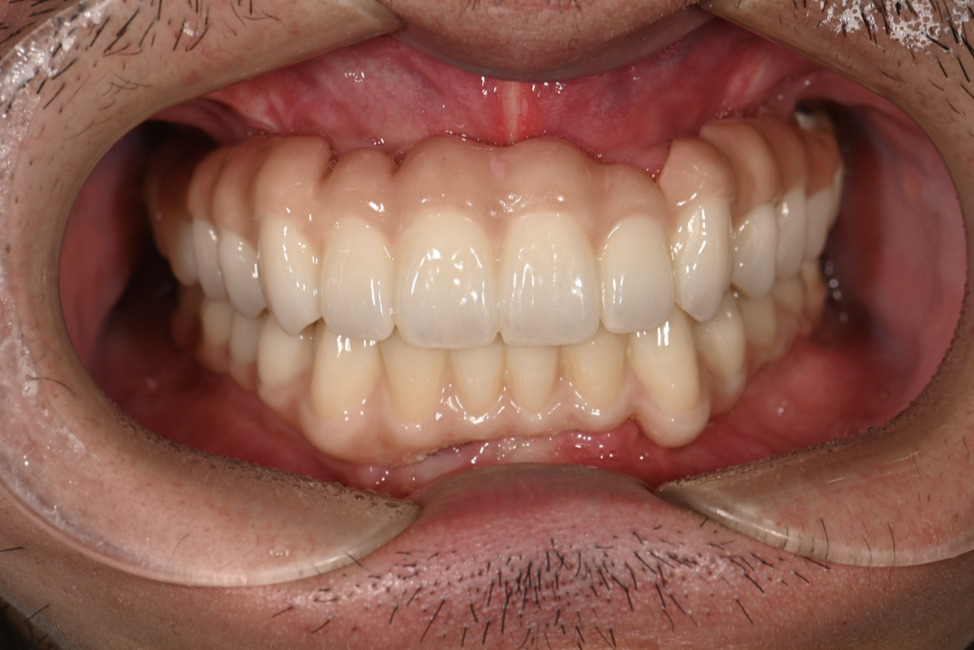

| 主訴 | 歯がグラグラして噛めない |

|---|---|

| 治療内容 | 上顎、下顎に対するインプラント治療 |

| 治療期間 | 1日 |

| 治療費 | 409万2千円 |

| 治療 リスク | 最終的な歯が入るまでは仮歯になります。 |